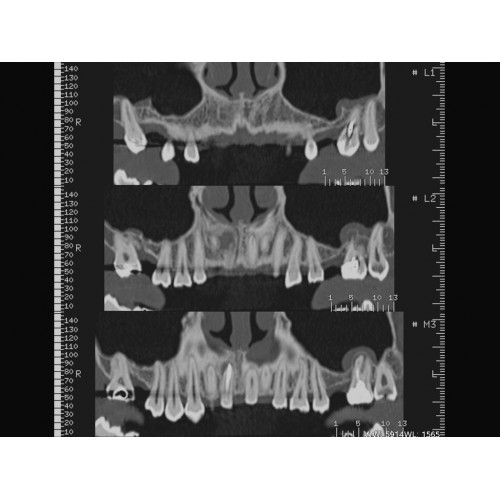

Неврологические исследования

• Выявление инсультов, опухолей головного мозга и травматических повреждений.

• Диагностика заболеваний позвоночника и межпозвоночных грыж.

Травматология и ортопедия

• Диагностика сложных переломов и повреждений суставов.

• 3D-реконструкция костных структур для планирования операций.